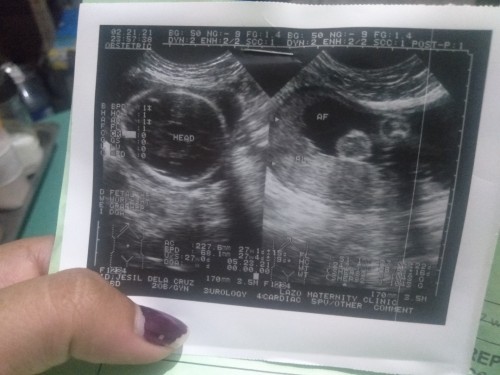

What position my baby

I'm 28week and 6days pregnant, nag Pa Ultrasound Kasi ako Sabi Ng OB ko baby Girl Naman Daw Kasi wla Naman silang makitang bayag if BBY boy automatic Naman Daw lalabas un. Kaya ask Ng OB ko baby Girl . Possible ba na mag kamali 😢 for the first time ko Sana mag karoon Ng baby girl may anak Kasi ako dlawa pareho boy.